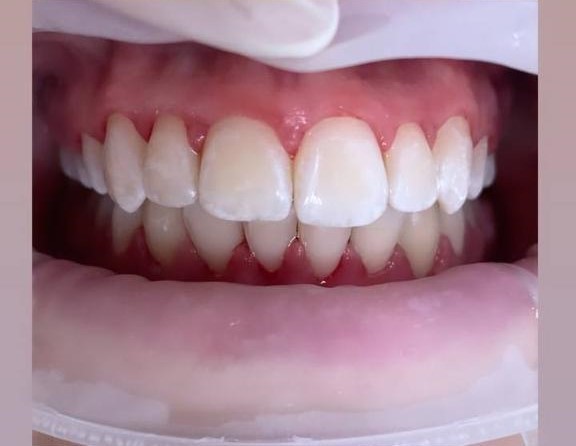

Установка брекетов

«Стеснялась улыбаться из-за промежутков между зубами»... Хотим поделиться с вами историей одной девочки, которая решилась поменять свою жизнь из-за дискомфорта во время улыбки. Девочка в возрасте 13 лет, попросила маму, прийти к ортодонту, чтобы скорректировать ее улыбку, так как ей не нравятся промежутки между зубами. Жалобы: - глубокий прикус - промежутки между зубами Было предложено лечение на элайнерах, так как это было бы удобнее и комфортнее для нее. НО девочка категорически отказалась! Она хотела, чтобы все видели, что она проходит ортодонтическое лечение. Поэтому было принято решение об установке наиболее видимой системы, а именно металлической брекет-системы. Лечение на брекет-системе заняло 1,5 года. За это время было сделано: - закрыты промежутки - уплотнены контакты - завершили лечение в правильном смыкании - зафиксировали несъемный ретейнер для удержания результата После снятия брекет-системы, девочке улыбка не нравилась в идеале, ей бы очень хотелось, чтобы ее зубы были крупнее. Сейчас мы отдыхаем, после ношения брекет-системы и проходим терапевтическую санацию полости рта. А далее, планируем коррекцию десневого контура, через хирургический шаблон, с помощью этого метода мы увеличим обьем белого и улыбка станет ярче!

Доктор: Кудрякова Динара Фяритовна